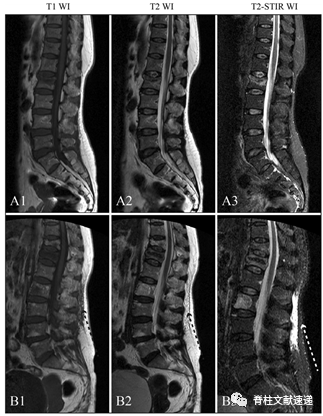

图注:没有伴随筋膜损伤的椎体压缩性骨折在T1 WI(A1)、T2 WI(A2)和T2-STIR WI(A3)MRI图像上无明显信号变化。伴有筋膜损伤的椎体压缩性骨折在 T1 WI (B1) 显示低信号,在 T2 WI (B2) 和 T2-STIR WI (B3) 显示高信号。